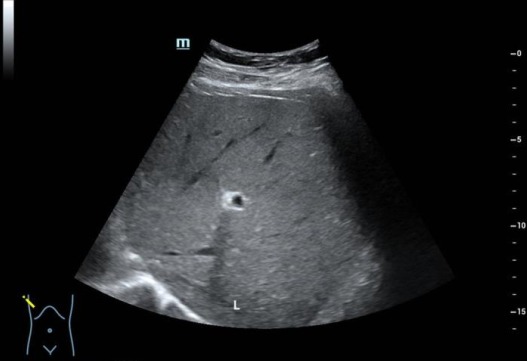

图 1 前年肝脏超声提示脂肪肝